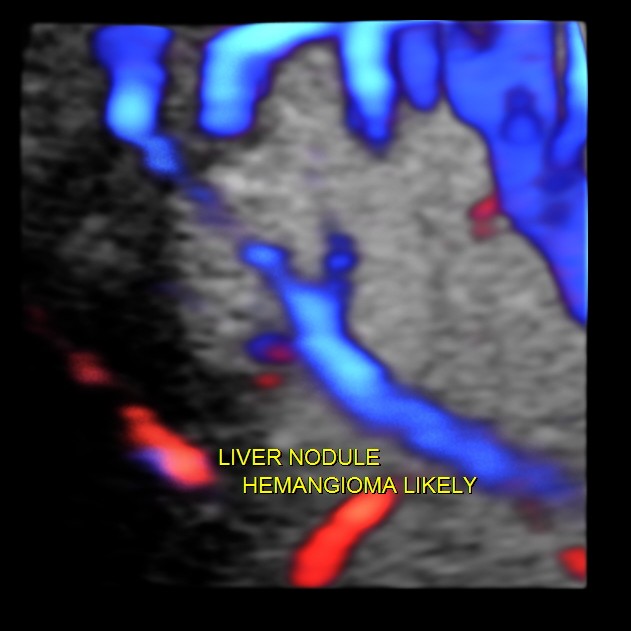

Hemangioma of the liver is generally an innocuous incidental finding . At times the differential diagnosis considered would include a solitary secondary nodule. This would require further imaging investigations like CT and MRI. Colour and Power Doppler could be helpful in demonstrating the feeding vessel to a hemangioma , but is very difficult to demonstrate at times. 3D 4 D glass body reconstruction could help in demonstrating the feeding vessel.

The pictures and the video are presented to show the clarity with which glass body reconstruction demonstrates the feeding vessel .